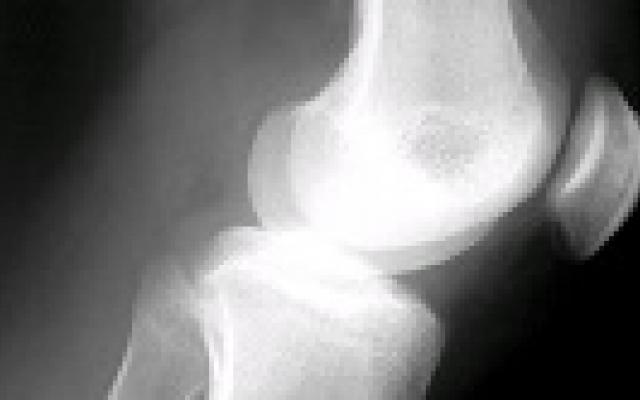

Dit artikel is alleen beschikbaar als PDF.Lees de PDF Artikelinformatie 24 maart 1960 Citeer dit artikel als Ned Tijdschr Geneeskd. 1960;104:1374-8 Heb je nog vragen na het lezen van dit artikel? Check onze AI-tool en verbaas je over de antwoorden. ASK NTVG Ook interessant Nieuws Over de behandeling van geschotene wonden in het heupgewricht Nieuws Diagnostiek der degeneratieve nieraandoeningen Nieuws Operatie voor degeneratief meniscusletsel verder in diskrediet Meer gerelateerd … Reacties Login om een reactie te plaatsen